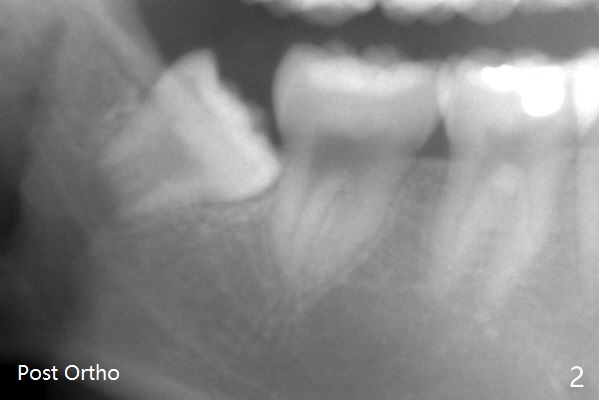

A 19-year-old man with history of orthodontic treatment (Fig.1,2) returns to office for #1,16,17,32 extraction with Collagen Plug placement at #17 and 32 (4-0 plain gut suture). The sockets heal in 4.5 months (Fig.3).